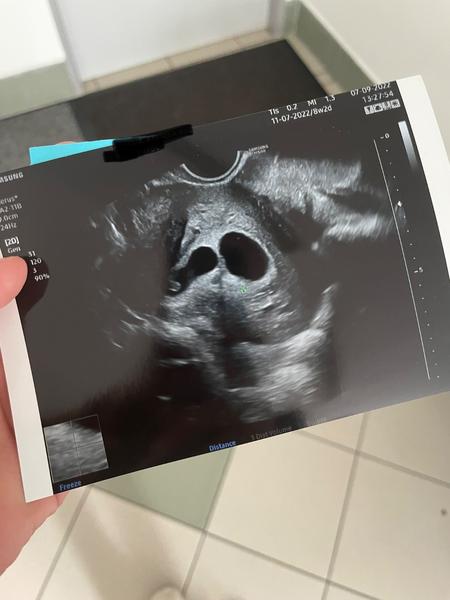

Mám čerstvě dvojčata, tady je skutečně jen jedno mimčo. Na mém ultrazvuku je sice mladší těhotenství (tohle bylo tak 7tt, podle MS to nevycházelo, měla jsem nepravidelné cykly), ale takhle vypadají dvojčata 🙂

@carameels a kde je to druhé? Vidim taky jen jedno 😁